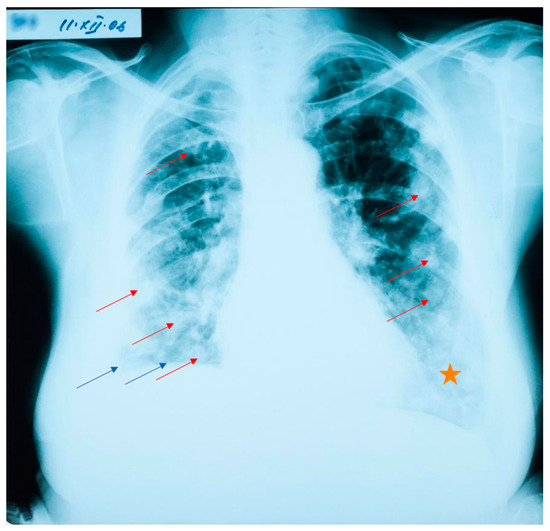

At her check-up in October 2006, the thoracic radiograph raised the suspicion of lung metastases from a cancer of unknown location (numerous 1–2 cm opacities, with bilateral lung dissemination) (Figure 1).

Thoracic and abdominal CT scans were performed, which revealed numerous thoracic masses, located in both the lungs and the pleura, round or oval in shape, centimetric or millimetric in size, with different consistencies, some liquid with calcifications, some condensed, sometimes clustering, as well as bilateral pachypleuritis, more pronounced on the right side (Figure 2).

Figure 1. Lung radiograph with numerous bilaterally disseminated opacities. Blue arrows show the elevation of the right diaphragm, and the blunting of the lateral costo-diaphragmatic angle. Red arrows point to round opacities disseminated bilaterally (not all are marked, as to not overcrowd the image). The orange star denotes an area with a diffuse para-cardiac opacity.